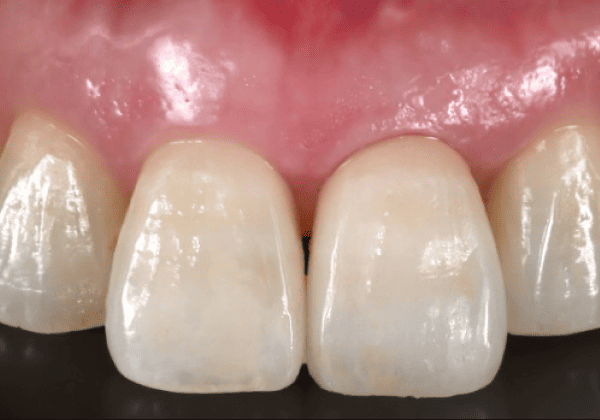

さらに、抜歯直後の歯ぐきの形を活かせるため、特に審美性が求められる前歯部では、自然な仕上がりが期待できるという利点もあります。歯がない期間を極力短くできるため、見た目や会話などに不安を抱える方にも安心してお選びいただけます。